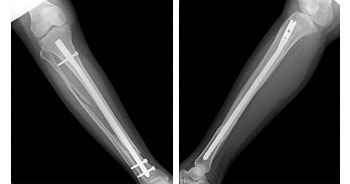

ADVANCED TRAUMA CARE

In any Trauma care center to receive and resuscitate the patient and to save life is our first priority. Saving the limb and other important organs is the next priority.

The hospital follows the principle of Triage, where by the patients are segregated by the surgeons as to have life threatening, limb threatening and other injuries depending on the type of injury, and are given treatment priority as the situation demands. To achieve this, a well-equipped intensive care unit and properly trained surgeons, anesthetists & Paramedical staffs are available, round the clock. Advance techniques in body warming, Sequential compression device, Alpha beds, and remote controlled ICU cots are available keeping the patients comfort in mind. Defibrillators, Ventilators, ABG analyzers, Cardio machine etc., are available to diagnose and prevent major complications.

• Trauma Surgery